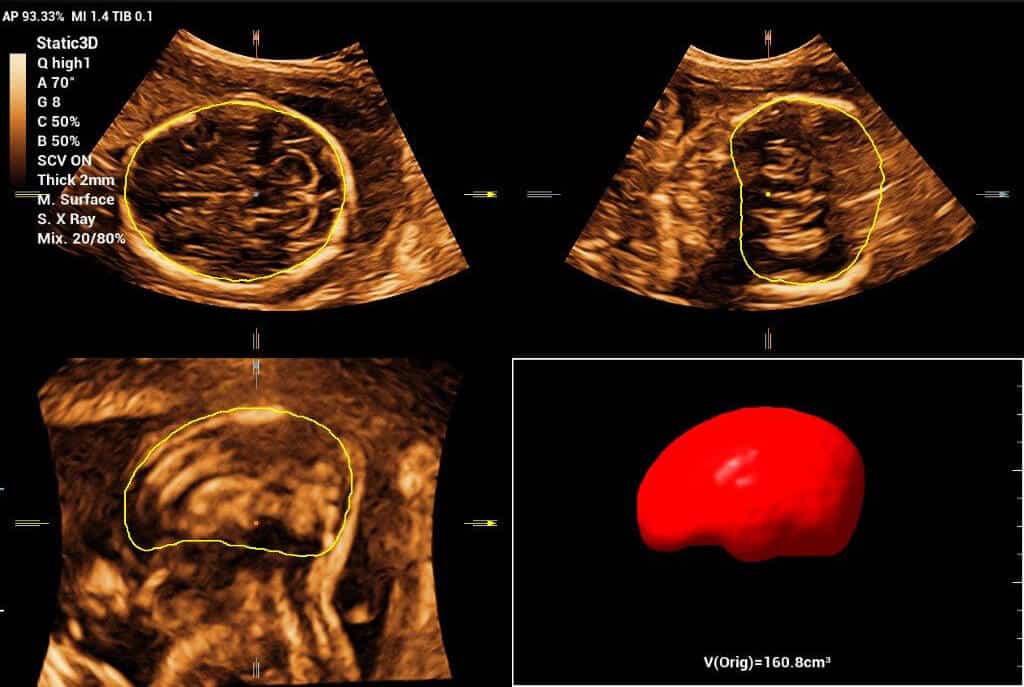

Powered by Mindray’s revolutionary ZONE Sonography (R) Technology+, the Imagyn I9 System boasts advanced ultrasound capabilities and leverages AI-inechanged technologies. The Imagyn I9 starts the process using auto clinical scenario identification, and uses automation at every point, from imaging optimization to planes scenario identification, and uses automation at every point, from imaging optimization to planes acquisition, quantification, and creating an automated workflow. The Imagyn I9 System provides a full-stack smart solution for efficient women’s health, covering wide-ranging applications from pre-pregnancy to obstetric to post-partum.